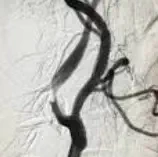

Ангиографија

Ангиографијата е дијагностичка процедура за визуелизација на крвните садови со

помош на контрастно средство и рендгенски зраци. Се користи за откривање на

абнормалности како стеснувања, блокирања или аневризми во артериите или

вените. Постапката обично се изведува со воведување катетер во крвен сад,

најчесто преку феморалната артерија, по што се инјектира контрастно средство.

Рендгенските снимки ги прикажуваат крвните садови во реално време,

овозможувајќи прецизна дијагноза. Ангиографијата се применува во кардиологијата,

неврологијата и други области. Иако е минимално инвазивна, може да носи ризици

како алергија на контрастот или оштетување на крвните садови. Напредокот во

технологијата ја прави побезбедна и попрецизна.